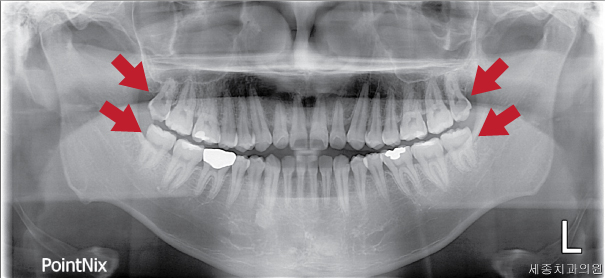

검진 결과 충치가 없던 정홍민 환자분이셨지만 발치해야할 사랑니가 4개가 있었는데요!

정홍민 환자분19.jpg

총 4개 사랑니 중  위에 위치한 사랑니 두 개는 섞어서 꼭 발치를 해야 하는 상황이고

아래 치아도 관리가 되지 않아 썩기 전에 발치를 해야합니다~

긴장 풀린지 5분 만에 다시 긴장을 하시는 정흥민 환자분!

하지만, 스케일링으로 인해 신뢰가 가셨던 건지, 사랑니 발치 예약까지 잡고 가셨답니다!

치과 진료를 제때 하지 못해서 사랑니 존재도 모르고, 썩었는지도 모르고 방치하게 된 상황인데요~

정기적인 검진은 여러분들의 치아건강을 지키는 일이랍니다!

다음편에는 정홍민 환자분의 리얼스토리 2탄! 사랑니 발치편도 많이 기대해주세요~~